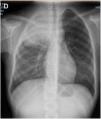

We present the case of a female patient aged 11 years, previously healthy, who presented with an interscapular mass, right-sided omalgia and constitutional syndrome of 6 months’ duration.1 The salient findings of the complete blood panel were leucocytosis with left shift and elevation of the erythrocyte sedimentation rate (ESR) and lactate dehydrogenase (LDH). The imaging evaluation confirmed a pulmonary pseudotumour extending beyond the lung with lung consolidation (Fig. 1, X-ray; Fig. 2, CT scan).